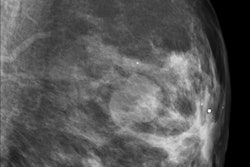

Radiologists at Maastricht University Medical Center believe that using gonad shielding may have more disadvantages than advantages. They compared 500 anterior-posterior (AP) pelvic radiographs taken in 2007 and 2008 using gonad shielding with 195 examinations taken in 2010 without gonad shielding. Their objective was to assess the quality of the images produced with respect to loss of diagnostic information and re-evaluate the benefit of shielding in terms of attainable radiation risk reduction (Insights into Imaging, 25 September 2011).

All the examinations for both time periods were performed using flat-panel DR systems (Axiom Aristos FX Plus, Siemens Healthcare). The systems had preprogrammed protocols, which set the high voltage (kVp), additional filter, focus to image-detector distance, and either a fixed tube current exposure (mAs) or the automatic exposure control (AEC). The protocols also indicated whether bucky antiscatter grids were needed. Age-dependent protocols with fixed technique parameters were used for children younger than age 10. Sized-based protocols were used for patients ages 10 to 15 years. The effective dose without gonad shielding ranged from 0.008 to 0.098 mSv.